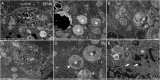

Electron microscopy is a powerful tool in the field of microbiology. It has played a key role in the rapid diagnosis of viruses in patient samples and has contributed significantly to the clarification of virus structure and function, helping to guide the public health response to emerging viral infections. In the present study, we used scanning electron microscopy (SEM) to study the infectious cycle of SARS-CoV-2 in Vero E6 cells and we controlled some key findings by classical transmission electronic microscopy (TEM). The replication cycle of the virus was followed from 1 to 36 h post-infection. Our results revealed that SARS-CoV-2 infected the cells through membrane fusion. Particles are formed in the peri-nuclear region from a budding of the endoplasmic reticulum-Golgi apparatus complex into morphogenesis matrix vesicae. New SARS-CoV-2 particles were expelled from the cells, through cell lysis or by fusion of virus containing vacuoles with the cell plasma membrane. Overall, this cycle is highly comparable to that of SARS-CoV. By providing a detailed and complete SARS-CoV-2 infectious cycle, SEM proves to be a very rapid and efficient tool compared to classical TEM.